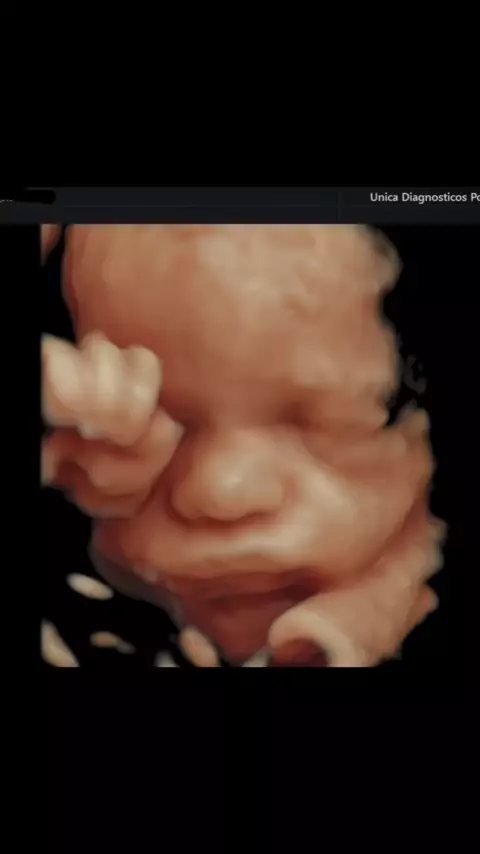

ultrassom 4D obstetrico.